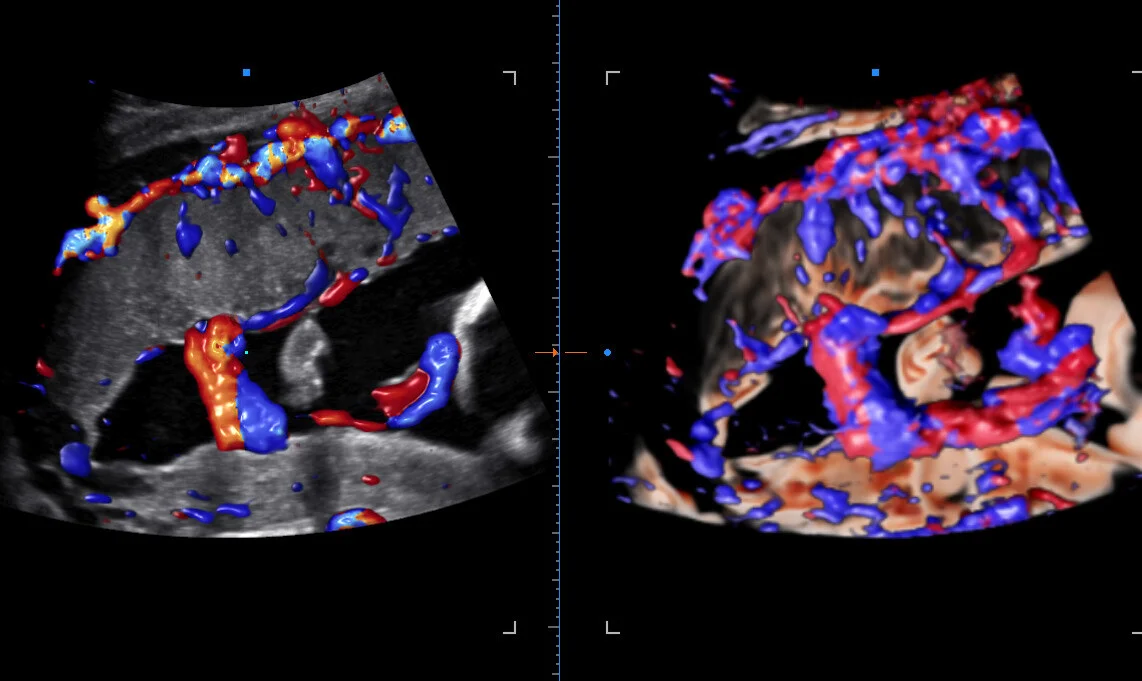

- Опция получения трехмерного изображения в режиме цветового допплеровского картирования ✔️

- Опция получения трехмерного изображения в режиме цветового допплеровского картирования (трехмерная реконструкция ЦДК) ✔️

- Crystal Vue™ / Crystal Vue Flow™ — прозрачная 3D-визуализация (Flow — объёмный кровоток).

- MV-Flow™ / MV-Flow 3D — визуализация микроциркуляции и медленного кровотока.

4. MV-Flow™ и LumiFlow™

MV-Flow показывает микроциркуляцию и медленный кровоток с высокой детализацией. LumiFlow добавляет объёмное отображение и направление потока, помогая лучше понимать сосудистую структуру тканей.